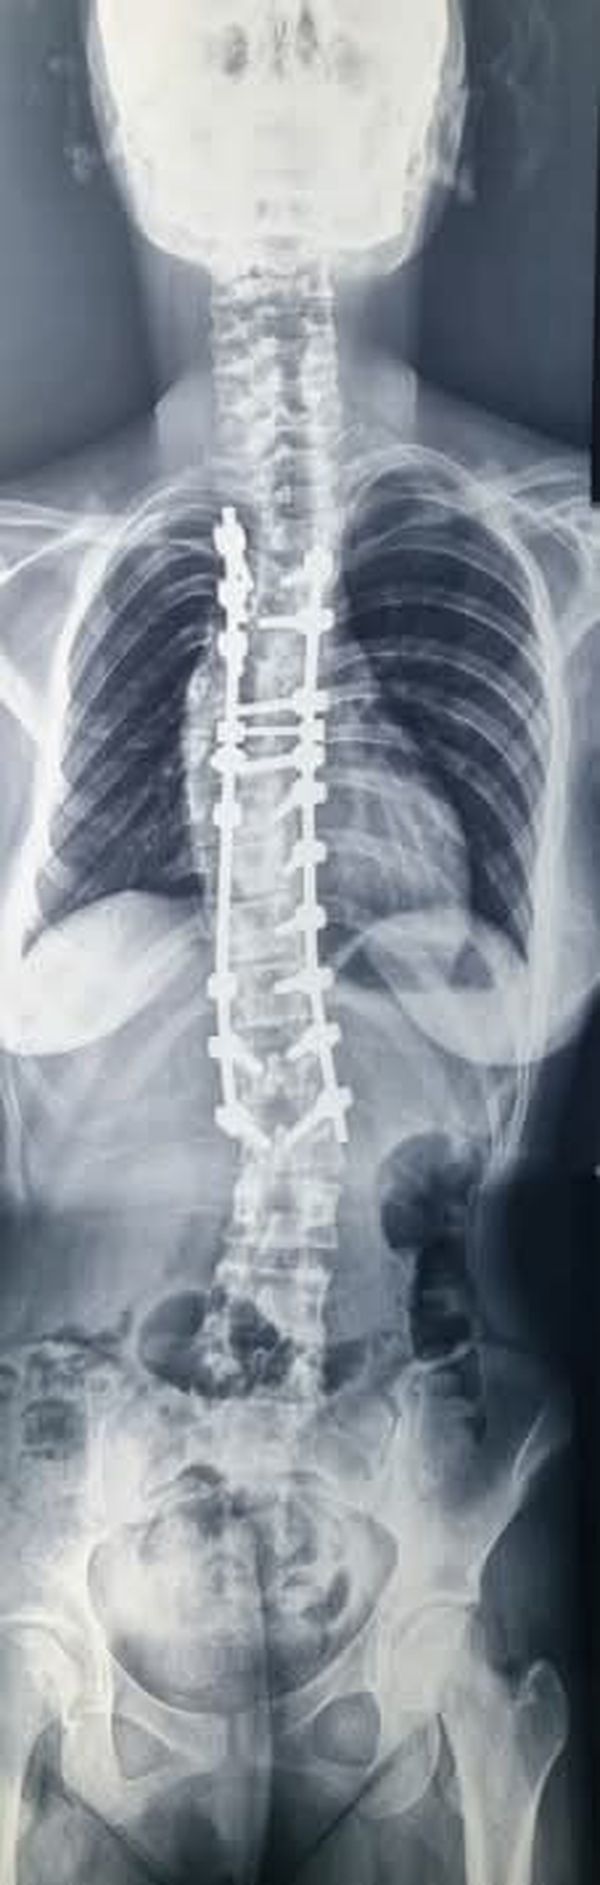

انت تتابع الان خبر فريق طبي بجامعة بني سويف ينجح في إصلاح اعوجاج بالعمود الفقري لأحد المرضى حصرياً والان نترككم مع التفاصيل

عدن - هند جمال - أعلن الدكتور طارق على ، القائم بأعمال رئيس جامعة بني سويف، نجاح فريق طبي بقسم جراحة المخ والأعصاب بكلية الطب في إصلاح اعوجاج في العمود الفقري لأحد المرضى، وهو ما يُعد علامة بارزة في مسيرة القسم نحو تقديم خدمة طبية متقدمة، وذلك تحت إشراف الدكتور هاني حامد عميد كلية الطب، والدكتور عماد البنا المدير التنفيذي للمستشفيات.

جانب من العملية الجراحية

وأوضح رئيس جامعة بنى سويف، أن الفريق الطبي الذى أجرى العملية الجراحية إصلاح اعوجاج في العمود الفقري لأحد المرضي، ضم الدكتور محمد شعبان محمود، أستاذ ورئيس القسم، والدكتور عبدالرحمن صابر المسؤول عن متابعة جراحات اعوجاج العمود الفقري، وبمشاركة كل من الدكتور مصطفى فكري و الدكتور محمود رمضان.

و هنأ رئيس الجامعة الفريق الطبي على هذا الإنجاز الطبي المتميز، الذي يُعد نموذجًا مشرفًا لما يمكن أن تقدمه الكفاءات الجامعية من خدمات صحية متقدمة، لافتاً إلى أن إجراء هذا النوع من العمليات التدقيقية يعكس مستوى التطور الذي وصلت إليه المستشفى الجامعي من حيث الإمكانيات البشرية والتقنية، مؤكدا حرص الجامعة الدائم على دعم كل الجهود التي تساعد في رفع جودة الخدمات المقدمة للمواطنين.